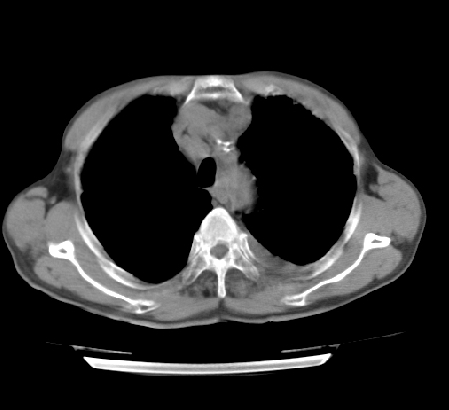

以下是引用hhcckk在2009-5-29 14:58:00的发言:[br]左上周围型肺癌,左肺门、纵隔淋巴结转移,左侧胸腔积液,左侧肋骨转移[br]

以下是引用ct诊断高手在2009-5-29 13:50:00的发言:[br]考虑左侧中央型肺癌,阻塞性肺炎伴肺不张。纵隔淋巴结转移。慢支 肺间质纤维化肺气肿。左侧胸腔积液。左侧肋骨转移?